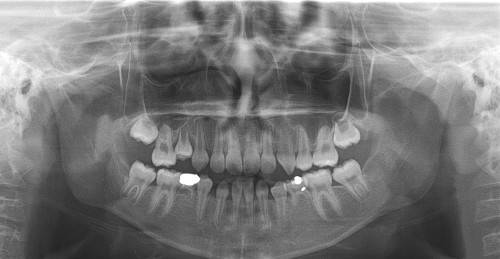

치과계는 수검자의 만족도를 높이고 낮은 수검률 문제를 근본적으로 해결하려면 현재 시행 중인 국가 구강검진 항목에 파노라마 방사선 촬영이 추가돼야 한다고 주장한다. 현재 구강검진에는 치과의사가 맨 눈으로 수검자의 치아 상태를 관찰하는 시진(視診)이 전부라 질병의 조기발견 능력이 떨어질 수밖에 없다는 것이다. 직장인 김모씨는 “직장인건강검진의 일환으로 치과병원을 가도 충치 몇 개 발견하는 게 전부라 매번 가야한다는 필요성을 느끼지 못한다”고 말했다. 현홍근 서울대치과병원 소아치과 교수는 “진료실에서 파노라마 촬영이 기본적으로 이뤄진다. 가장 일반적인 검사방법이 국가 구강검진에는 빠져있어 치아우식증, 치주병, 치아손실, 구강암, 물혹 등을 발견하기 어렵다”고 말했다.

치과에서 사용 중인 파노라마 방사선기기는 1차 개원병원에 98% 보급돼 있을 만큼 진료를 위해서는 기본적으로 행해지는 검사방법이다.

그러나 국가 구강검진에는 시진만 하도록 돼있어 심한 충치를 발견하는 데 그친다는 지적이 나온다.

허민석 서울대치과병원 영상치의학과 교수는 “눈으로 봐서 보이는 질환과 파노라마방사선촬영을 통해 보이는 질환의 수 차이가 크다. 치아와 치아가 맞닿은 부위에 발생하는 인접면 치아우식증은 파노라마방사선촬영이 아니라면 발견하기 어렵다”고 말했다. 허 교수는 “육안으로는 건강한 치아상태를 보이신 어르신이 어느 날 치아가 뽑혀왔다”며 “겉으로는 멀쩡해보여도 속으로는 잇몸뼈가 녹고 있었던 것이다. 노인에서 흔한 증상이지만 이는 파노라마 촬영이 아니라면 알기 어렵다”고 지적했다.

현홍근 교수는 “파노라마 촬영으로 피폭되는 방사선량은 3∼24 나노시버트에 불과하다. 이는 흉부엑스레이 촬영과 견줘 상당히 낮은 수치지만 이를 통해 확인할 수 있는 치주질환의 수가 많다”며 “매복치, 과잉치를 앓는 소아환자의 수를 감안한다면 예방이 가능한 효과적인 검진방법의 도입이 절실하다”고 반박했다.